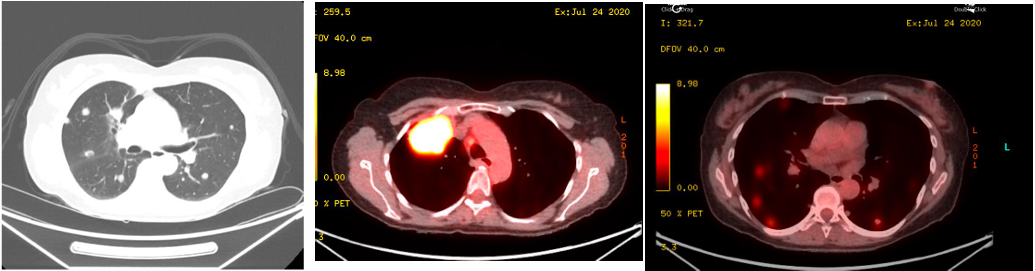

2021年5月,患者因右肺上叶主结节出现孤立性进展,接受立体定向放射治疗(SBRT),剂量为55Gy,分10次照射。治疗后,无进展生存期(PFS)达12个月,展示局部巩固治疗在控制寡进展中的有效性。然而,2022年6月,患者在维持免疫治疗期间,右肺下叶和左肺下叶出现新病灶,接受SBRT治疗,剂量分别为62.5Gy(分10次)和50Gy(分5次,每次10Gy,隔日一次)。同年7月,患者出现左额叶脑转移,经手术切除后,接受SBRT至切除腔,剂量为27Gy(分3次),每次9Gy。这表明,对于寡转移病灶,局部巩固治疗能够有效延长患者的PFS。

c519c15b-fb4b-412a-9bd5-51e05d973e6a.png